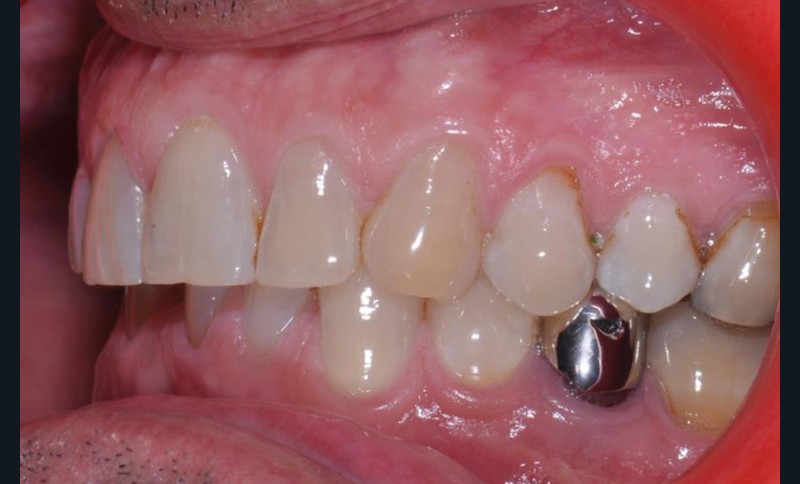

Présentation du cas clinique (fig. 1 à 3)

Le patient, âgé de 58 ans, présente un encombrement dentaire mandibulaire de 5 mm dans un contexte squelettique hypodivergent.